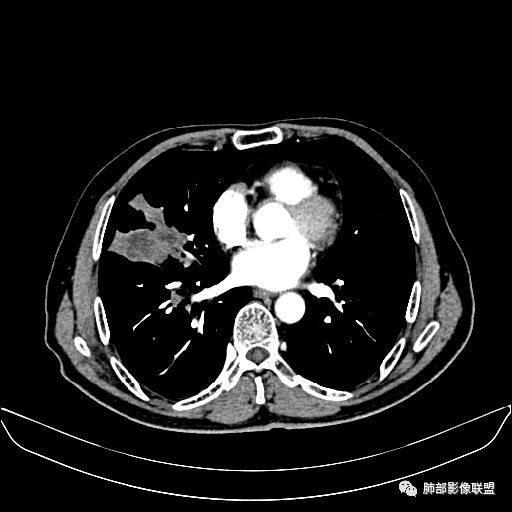

住院4天后行胸部增强CT

动脉期